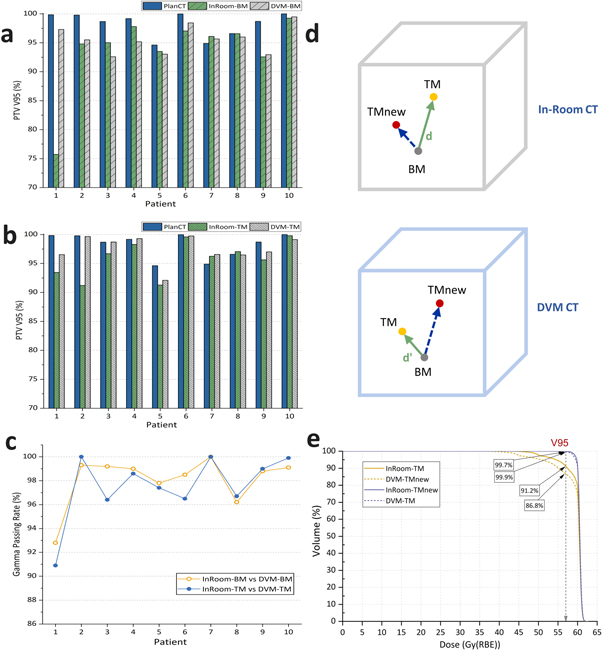

A summary of the dose distribution comparison between the DVM CT and in-room CT for each HCC patient is shown in figure 6, tables 1 and 2. Moreover, the dose distribution of a representative patient is illustrated in figure 7. Between the in-room CT and DVM CT, the PTV coverage (V95%) differences were less than 3%, except for Patient 1 in the BM scenario and Patient 2 in the TM scenario, and the normal liver (total liver minus GTV) dose differences (V20Gy(RBE) and V10Gy(RBE)) were less than 2% (V20Gy(RBE) and V10Gy(RBE) were 0.28 ± 0.62% and 0.14% ± 0.68% for BM and 0.20 ± 0.26% and 0.08 ± 0.30% for TM, respectively). The gamma passing rates with a 3%/3 mm criterion were above 90% in all cases and above 96%, excluding Patient 1.

Figure 6. Planning target volume (PTV) coverage (V95%) comparisons in the bone (a) and tumor (b) matching scenarios for individual patients and their gamma passing rates with criterion 3%/3 mm (c). (d) illustrates the distances between the isocenters of BM and TM in the in-room CT and the DVM CT. (e) shows the dose-volume histogram (DVH) of InRoom-TM, DVM-TMnew, InRoom-TMnew, and DVM-TM for Patient 2. TMnew represent the new isocenters considering  in (d).

in (d).

Standard image High-resolution imageFor Patient 2 in the TM scenario, the PTV coverage of the InRoom-TM was significantly lower than that of the InRoom-BM, unlike the other nine cases, which were approximately equal. This may be because the marker shifts inside the liver did not always represent the motions of the entire liver and/or tumor; the distance between the isocenters of BM and TM in the in-room CT and the DVM CT was different by 4.2 mm ( in figure 6(d)) for Patient 2, i.e. the isocenter position of TM in the in-room CT was considerably different from that determined by DVM CT. Applying the difference to determine the new isocenter for InRoom-TM, the new dose distribution for InRoom-TM (InRoom-TMnew, called Patient 2a) could be obtained by recalculating the dose based on the new isocenter. By comparing InRoom-TMnew to DVM-TM, the PTV coverage difference decreased to 0.25%, which was considerably lower than the PTV coverage difference between InRoom-TM and DVM-TM (−8.45%). Conversely, obtaining the new dose distribution the same way as the above for DVM-TM (DVM-TMnew, called Patient 2b), the PTV coverage difference between InRoom-TM and DVM-TMnew decreased to 4.46%. The PTV coverage comparisons between PlanCT, InRoom-TM, DVM-TMnew, InRoom-TMnew, and DVM-TM for Patient 2 are presented in figure 6(e).

in figure 6(d)) for Patient 2, i.e. the isocenter position of TM in the in-room CT was considerably different from that determined by DVM CT. Applying the difference to determine the new isocenter for InRoom-TM, the new dose distribution for InRoom-TM (InRoom-TMnew, called Patient 2a) could be obtained by recalculating the dose based on the new isocenter. By comparing InRoom-TMnew to DVM-TM, the PTV coverage difference decreased to 0.25%, which was considerably lower than the PTV coverage difference between InRoom-TM and DVM-TM (−8.45%). Conversely, obtaining the new dose distribution the same way as the above for DVM-TM (DVM-TMnew, called Patient 2b), the PTV coverage difference between InRoom-TM and DVM-TMnew decreased to 4.46%. The PTV coverage comparisons between PlanCT, InRoom-TM, DVM-TMnew, InRoom-TMnew, and DVM-TM for Patient 2 are presented in figure 6(e).

The dose coverage differences between InRoom-BM and DVM-BM were 0.42 ± 1.35%, excluding Patient 1; they were −0.46 ± 0.91% between InRoom-TM and DVM-TM, excluding Patient 1 and replacing Patient 2 with Patient 2a. The same trend can be seen in the clinical data as in the phantom data that the dose coverage of the DVM CT changed consistently with those of the in-room CT with different isocenters. The results showed that the DVM CT was similar to the in-room CT for liver cases; therefore, DVM CT is sufficiently representative of in-room CT for evaluating dose distributions for liver cases.

The CTV and PTV coverage comparisons of five patients simulating large inter-fractional motions are shown in figure 8 and table 1. CTV coverage differences between InRoom-BM and DVM-BM and between InRoom-TM and DVM-TM were 2.18 ± 2.82% and −0.24 ± 0.42%, respectively. PTV coverage differences between InRoom-BM and DVM-BM and between InRoom-TM and DVM-TM were 1.59 ± 3.36% and −0.7 ± 1.6%, respectively. The dose coverage differences between in-room CTs and DVM CTs were small in both BM and TM scenarios. The magnitude of the change in dose coverage of the DVM CT followed that of the in-room CT at different isocenters in all selected patients. This indicated that in-room CTs and DVM CTs had high similarities in dose distribution, and the DVM technique could be applied to patient data with relatively large inter-fractional motions. The dose coverage differences between InRoom-TM and DVM-TM were slightly smaller than those between the InRoom-BM and DVM-BM. A possible reason for this is that the proportion of the CTV/PTV located on the steep dose gradient region was higher for BM than TM, making the dose coverage sensitive to small displacement differences.